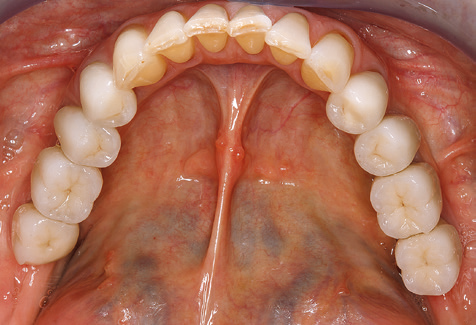

Abb. 9: Die Politur der zugänglichen Implantat­ und Zahnoberflächen erfolgt mit Polierkelchen und geeigneten Polierpasten. – Abb. 10: Die Reinstruktion zur Anwendung geeigneter Hilfsmittel bei der häuslichen Mundhygiene sollte ebenfalls Bestandteil der UPT sein. – Abb. 11a und b: Klinische Situation zwölf Jahre nach Insertion der prothetischen Versorgung. In diesem Zeitraum kam es lediglich zu einer Verblendkeramikfraktur am Zahn 47 und der Notwendigkeit einer endodontischen Behandlung am Zahn 12. Sämtliche Restaurationen sind noch in Funktion.

Für den klinischen Langzeiterfolg des parodontal kompromittierten Patienten ist die standardisierte und regelmäßige risikoadaptierte Betreuung im Rahmen der UPT der zentrale Baustein des Behandlungserfolgs. Dies gilt in besonderer Weise für Patienten, die nach erfolgreich abgeschlossener parodontaler Sanierung mit Implantaten versorgt wurden (Abb. 11a und b).